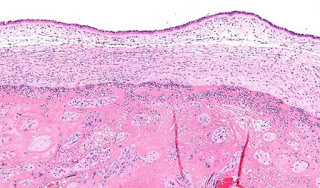

High magnification micrograph chorioamnionitis. (CC BY-SA 3.0)

The physical evidence, she says, suggests the cause of the woman's death, which occurred in the waning decades of the Byzantine Empire, was chorioamnionitis, a bacterial infection of the placenta, amniotic fluid and membranes surrounding the fetus. In addition to the woman's DNA, and that of the bacteria causing her infection, researchers identified ancient Y chromosome DNA, likely that of a male fetus. "Quite a few women died from complications during pregnancy and childbirth," notes Kiesewetter, a co-author of the eLife report.